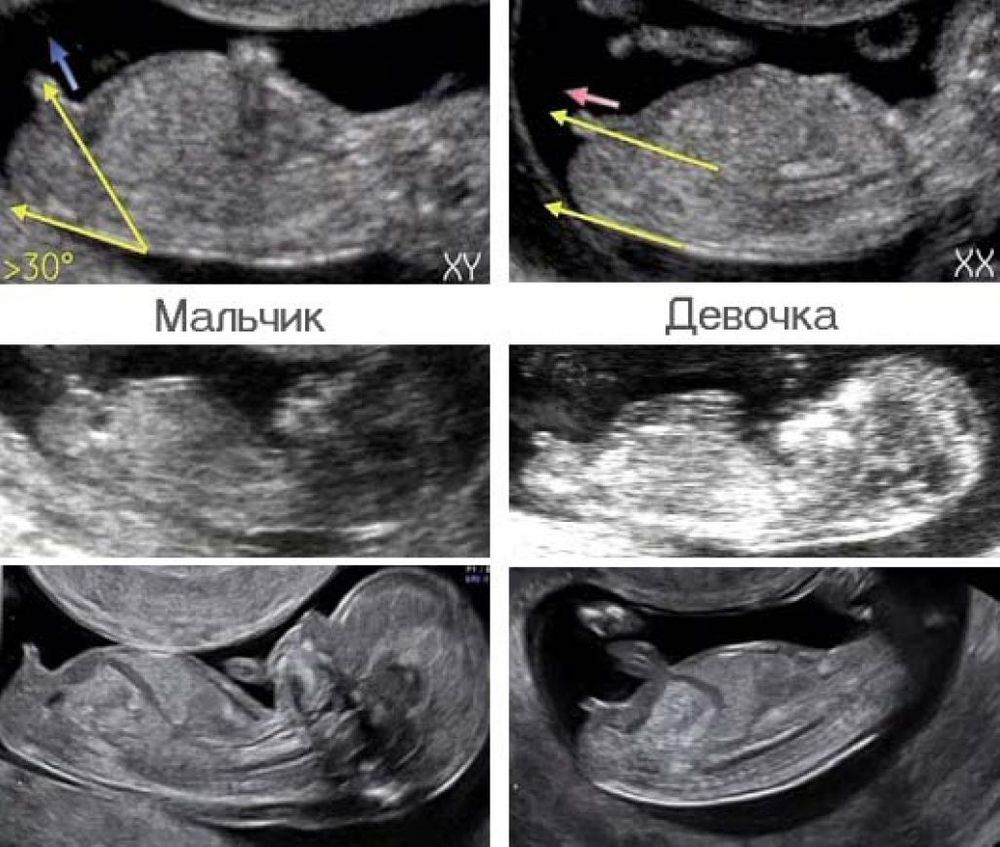

Валерия Воликова, потому так и сказала, что до 16 недель это все гадания на кофейной гуще. Фото должно быть снизу, чтоб промежность видно было. типа этого.

а сбоку и по взрослым не всегда поймешь😂

Katerinka, вот такие бугорки.

Я слов на ветер не бросаю.

Просто узист должен быть спецом, чтобы видеть точно угол наклона бугорка, а так, конечно, обычно не говорят либо предполагают, но с вероятностью 50%😊